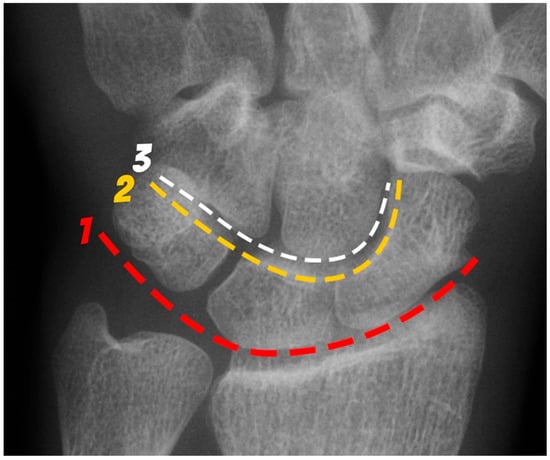

The next most common carpal fracture is the triquetral fracture. Most of these occur on the dorsal aspect of the triquetrum and are best identified on the lateral radiograph at the dorsal aspect of the triquetrum and are best identified as the so-called “pooping duck sign”. These result from compression of the ulnar styloid process and the dorsal aspect of the triquetrum during forceful ulnar deviation and wrist hyperextension [4,5]. Triquetral fractures are subdivided into body, volar cortex, and dorsal cortex fractures, with the latter being the overwhelming majority. Triquetral body fractures (Figure 10a,b) are injuries that are often associated with intrinsic ligamentous injury, such as a lunotriquetral tear. Dorsal cortex fractures (Figure 10c) represent avulsions of the combined attachment of the dorsal radiocarpal and dorsal intercarpal ligaments. Management of dorsal cortex fractures and nondisplaced body fractures consists of 3 to 6 weeks of cast immobilization. If there is concomitant intrinsic ligamentous injury such as a lunotriquetral ligament tear, this injury is unstable and requires surgical stabilization [17].

Figure 10. (a) PA radiograph of the wrist showing a triquetral body fracture (arrow) and concurrent scaphoid fracture (arrowhead). (b) Coronal reformatted CT confirms these findings with greater detail. (c) Lateral radiograph of the wrist showing a dorsal cortex fracture of the triquetrum with a tiny, avulsed fragment (curved arrow).